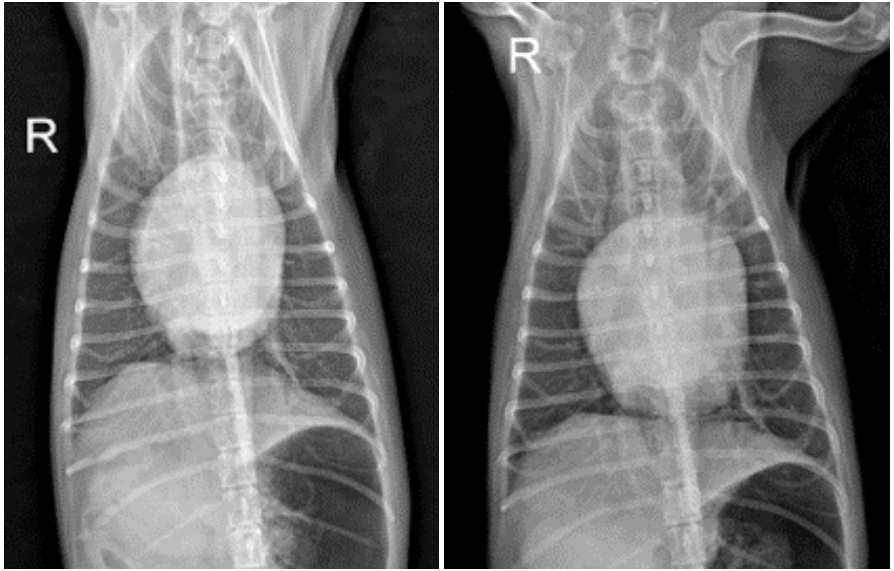

호흡과 혈압 상태가 계속해서 양호하게 유지되었고, 흉부 방사선 검사에서 심장과 좌심방의 크기, 폐 침윤이 의미 있게 감소한 것이 확인되었습니다. 이에 따라 이뇨제의 지속 정맥 주입(CRI)을 중단하고, 정맥 주사로 감량하여 유지 치료를 진행하였습니다. ▼

3. 입원 4일차

폐 침윤이 소실되며 폐야가 정상화되었고, 호흡 양상도 안정적인 상태를 유지하였습니다. 염증 수치 역시 호전되어 항생제를 중단하였으며, 상태가 충분히 안정된 것을 확인한 후 내복약으로 전환하여 통원 치료로 전환하였습니다.

입원 3일차(좌), 입원 4일차 (우)